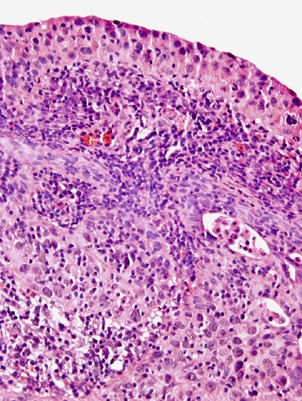

Seventeen cases (57%) had pure lymphoepithelioma-like carcinoma with the remaining cases having lymphoepithelioma-like carcinoma with other patterns of carcinoma (Table 1). The epithelial component of lymphoepithelioma-like carcinoma consisted of nests and individual cells of undifferentiated carcinoma admixed with a prominent often-obscuring inflammatory infiltrate (Figures 1, 2 and 3). In two cases, <1% of the tumor had glandular differentiation in an otherwise typical lymphoepithelioma-like carcinoma, where the glandular element merged with the typical lymphoepithelioma-like carcinoma and the glandular elements were heavily infiltrated by lymphocytes identical to typical lymphoepithelioma-like carcinoma and in contrast to adenocarcinoma associated with lymphocytes (Figure 4). In two other cases, the epithelial component of lymphoepithelioma-like carcinoma was focally composed of clear cells (Figure 5). Of the 13 cases without pure lymphoepithelioma-like carcinoma, the associated conventional carcinoma component was invasive urothelial carcinoma (n=10), invasive adenocarcinoma (n=3), and squamous cell carcinoma (n=2) (some tumors with more than one non-lymphoepithelioma-like carcinoma component). In addition to lymphoepithelioma-like carcinoma, the surface demonstrated carcinoma in situ (CIS) in six cases, noninvasive high-grade papillary urothelial carcinoma in three cases, and in situ adenocarcinoma in one case (Figures 6 and 7). Either invasive or noninvasive urothelial carcinoma was associated with lymphoepithelioma-like carcinoma in 14/30 (47%) cases (Table 1). In 19/30 (66%) cases, the inflammatory component consisted of a heavy lymphocytic infiltrate and in the remaining 11/30 (34%) cases a mixed inflammatory infiltrate composed of neutrophils, eosinophils, lymphocytes, histiocytes, and plasma cells (Figures 1 and 8).